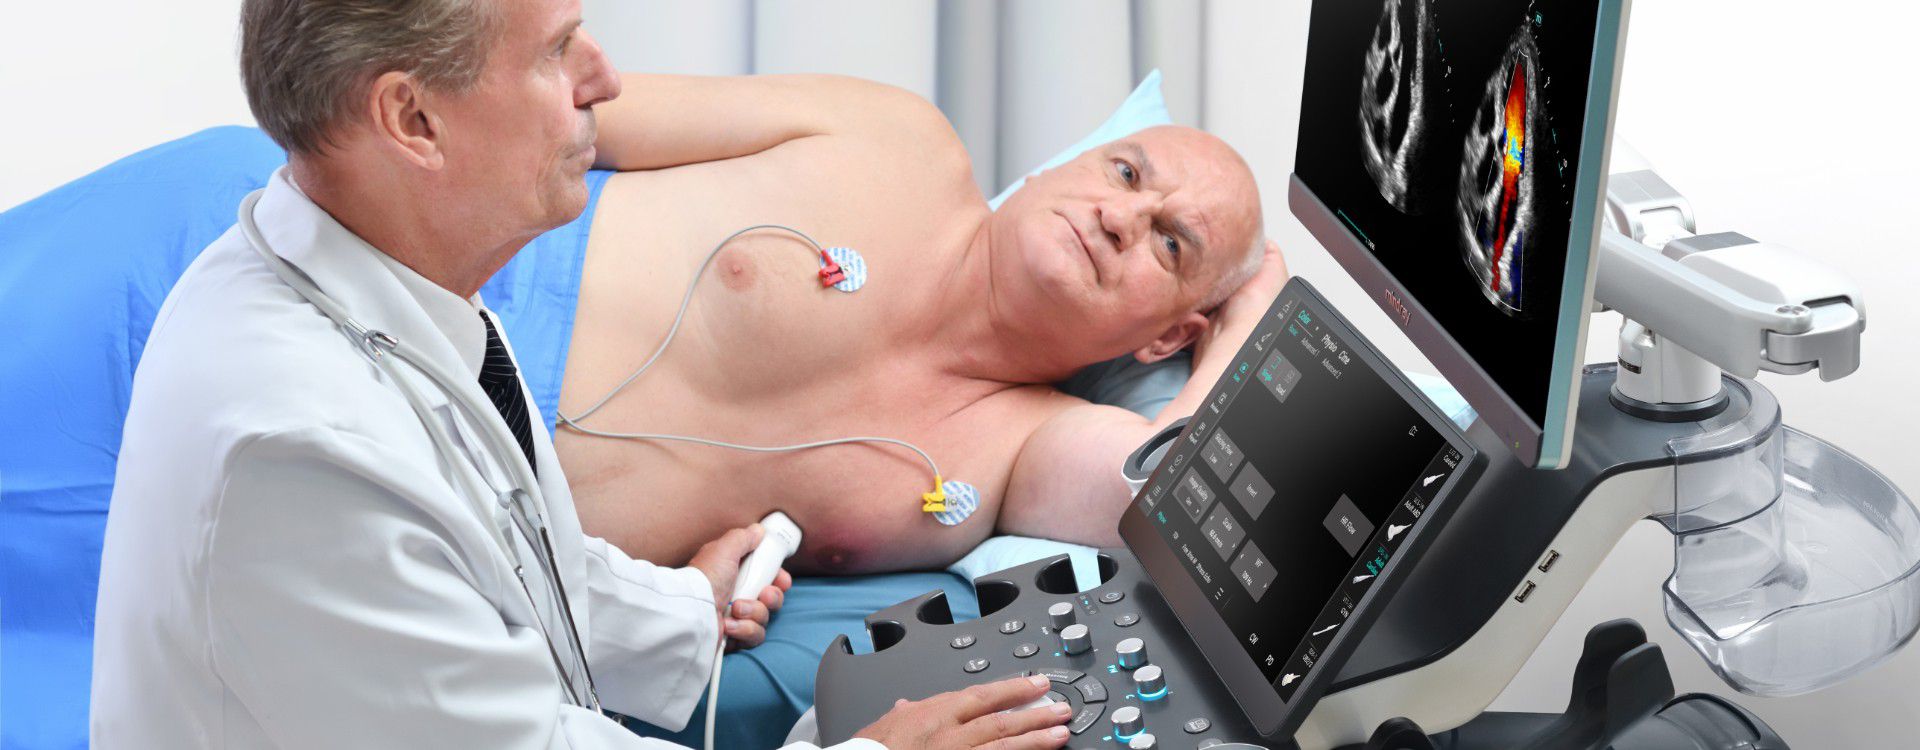

Sistema diagnostico a ultrasuoni

Serie Consona N

Consona presenta soluzioni nuove e concrete, che aiutano a effettuare diagnosi efficaci con semplicitĂ , rivolgendosi a un'ampia platea di pazienti. La serie mette a disposizione strumenti estremamente avanzati per rimanere all'avanguardia nella diagnosi cardiovascolare.